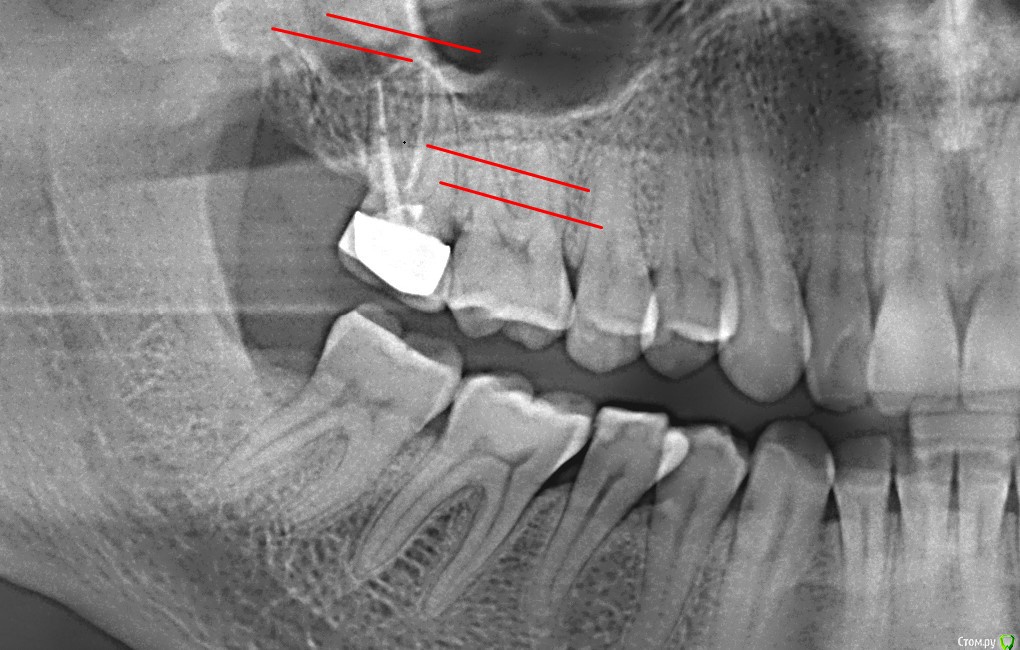

AlexNick Опубликовано 24 сентября, 2017 Автор Поделиться Опубликовано 24 сентября, 2017 Снимок - во вложении. Красным показана примерная локализация боли. Ссылка на комментарий

DmitrySH Опубликовано 24 сентября, 2017 Поделиться Опубликовано 24 сентября, 2017 В седьмом зубе желательно обработать и запломбировать все каналы. Ссылка на комментарий

AlexNick Опубликовано 24 сентября, 2017 Автор Поделиться Опубликовано 24 сентября, 2017 Дело в том, что этот зуб был пролечен ещё 10 лет назад резорцин-формалиновым методом. Мне сказали, что через такой длительный срок он уже "мумифицирован" и больше лечению не подлежит. И даже коронку с него снять очень проблематично. Рекомендовали "не трогать". Можно ли в этом случае выяснить причину боли, "не вскрывая" седьмой зуб? Вдруг причина в чём-то другом. Ссылка на комментарий

DmitrySH Опубликовано 30 сентября, 2017 Поделиться Опубликовано 30 сентября, 2017 Можно ли в этом случае выяснить причину боли, "не вскрывая" седьмой зуб? Вдруг причина в чём-то другом. сделайте КТ, будет информативнее. Мне сказали, что через такой длительный срок он уже "мумифицирован" и больше лечению не подлежит. И даже коронку с него снять очень проблематично. глупости Коронку"снимать"не надо. Распилить и выкинуть. Работы на несколько минут.Резорцин в большинстве случаев без проблем можно распломбировать. Ссылка на комментарий